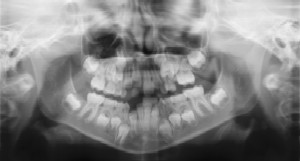

Radiographs (X-Rays) are a vital and necessary part of your child’s dental diagnostic

process. Without them, certain dental conditions can and will be missed.

Radiographs detect much more than cavities. For example, radiographs may be needed to survey erupting teeth, diagnose bone diseases, evaluate the results of an injury, or plan orthodontic treatment. Radiographs allow dentists to diagnose and treat health conditions that cannot be detected during a clinical examination. If dental problems are found and treated early, dental care is more comfortable for your child and more affordable for you.

The American Academy of Pediatric Dentistry recommends radiographs and examinations every six months for children with a high risk of tooth decay. On average, most pediatric dentists request radiographs approximately once a year. Approximately every 3 years, it is a good idea to obtain a complete set of radiographs, either a panoramic and bitewings or periapicals and bitewings.

Pediatric dentists are particularly careful to minimize the exposure of their patients to radiation. With contemporary safeguards, the amount of radiation received in a dental X-ray examination is extremely small. The risk is negligible. In fact, the dental radiographs represent a far smaller risk than an undetected and untreated dental problem. Lead body aprons and shields will protect your child. Today’s equipment filters out unnecessary x-rays and restricts the x-ray beam to the area of interest. High-speed film and proper shielding assure that your child receives a minimal amount of radiation exposure.